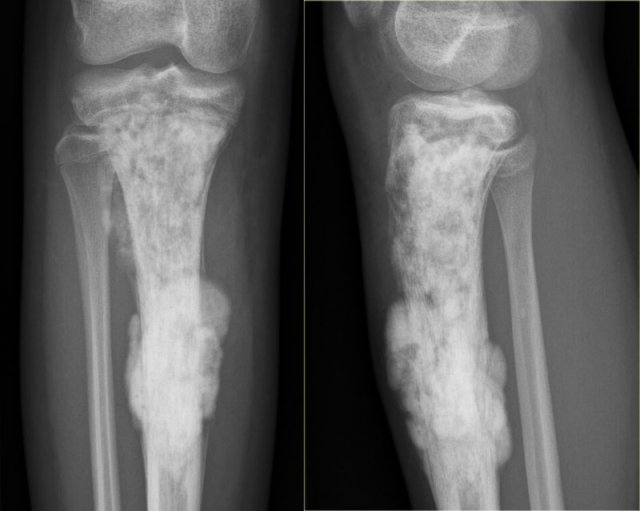

Chondrosarcoma

Low-grade chondrosarcoma Low-grade chondrosarcoma

The image shows a calcified lesion in the proximal tibia without suspicious features.

This could very well be an enchondroma.

There were other features that favored the diagnosis of a low-grade chondrosarcoma like a positive bone scan and endosteal scalloping of the cortical bone on an MRI (not shown).

A chondrosarcoma was diagnosed at biopsy.